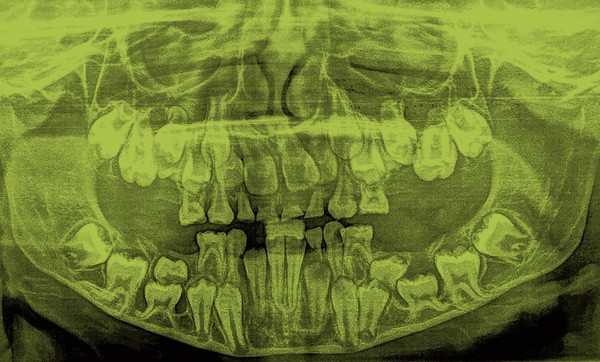

Marine consulte, avec une radiographie panoramique (fig. 1), au service d’Odontologie du CHU de Bordeaux. Elle est adressée par son chirurgien-dentiste pour un important retard d’évolution dentaire.

Radiographie panoramique

La radiographie panoramique confirme la présence de tous les germes et le retard d’évolution dentaire, mais révèle la présence des deuxièmes molaires mandibulaires temporaires incluses en position basale sous les germes des deuxièmes prémolaires permanentes. Elles présentent, comme les premières molaires mandibulaires, elles aussi incluses en position très basale, des racines très courbées au voisinage de la corticale.

Les premières molaires maxillaires sont également incluses, comme les deuxièmes molaires temporaires qui se superposent aux germes des deuxièmes prémolaires permanentes, en position apicale par rapport à ces dernières. L’interrogatoire confirme que les deuxièmes molaires temporaires maxillaires et mandibulaires n’ont jamais fait leur éruption.